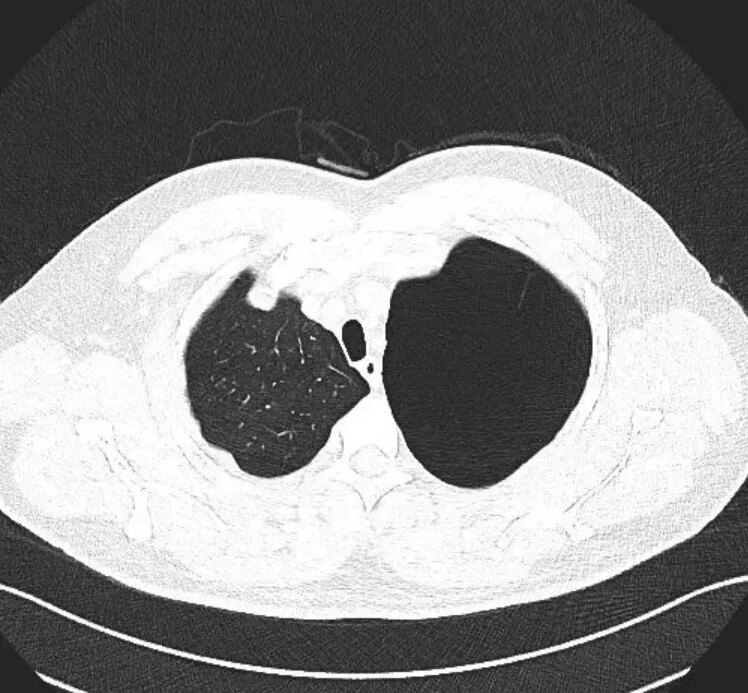

最近常常有患者拿着胸部CT来咨询关于肺大泡的一些问题,很多人在网上查阅资料后发现肺大泡无法用药根治,顿时茶饭不思,在这里我们带大家正确认识肺大泡。什么是肺大泡?肺大泡,是指由于各种原因导致肺泡腔内压力升高,肺泡壁破裂,互相融合,在肺组织形成的含气囊腔。肺大泡定义为扩张状态下,直径超过1cm的肺内气腔(图1),巨型肺大泡是指至少占据一侧胸腔30%的大泡(图2)肺大泡的常见原因是什么?1.气管的炎性病变如肺炎、肺结核、慢性支气管炎等,因炎性病变,气管出现水肿、狭窄,造成管腔部分阻塞,产生活塞作用,空气能进入肺泡而不易排出去,使之肺内压增高。2.吸烟、空气污染对于长期吸烟及其他有害气体和职业粉尘吸入史的患者,人体在吸入这些有害的气体、细颗粒物后,这些物质经过气管、细支气管,最终在肺泡停留沉积下来,它们会长时间的刺激、破坏正常的肺泡结构,肺泡壁破裂,从而形成肺气肿,随着破坏的进一步持续,这些肺气肿也将进一步破坏,融合成片,从而最终形成肺大泡。3.原发性肺大泡原发性肺大泡,可能与肺发育不良有关,多见于体形瘦高的青少年,其原因可能与青春期发育过程中,骨骼生长过快,肺相对生长缓慢,在胸顶和肺尖部有一个筋膜过渡牵拉肺尖部组织,导致该处肺组织的肺泡发育不良形成肺大泡。肺大疱如何治疗呢?肺大泡一种不可逆转的肺部病损,一般不能自愈,且目前尚无特效药物治疗,手术是治疗肺大泡唯一有效的方法,但不是所有的肺大疱均需手术质量。如一些较小的、局限的、数量少的肺大泡,多不会引起临床症状,通常不需要治疗。由气道炎症、肺气肿等病变导致的肺大泡,需要积极治疗原发病。肺大泡如果大于胸腔的1/3,就被称为巨大的肺大泡,可能对周围的组织形成较大的压迫,甚至对生命产生威胁,这种情况要尽快进行手术治疗。肺大疱患者的注意事项1.吸烟及空气污染是肺气肿的首要诱因,因此远离烟草及空气污染能够减缓进程;2.平时不要做剧烈的运动,不要手提重物,不要突发性的大声咳嗽及大笑,避免肺大泡破裂,产生自发性气胸;3.适当锻炼身体,增强身体的抵抗力和免疫力,根据自身情况,参加一些适当的体育活动,注意营养,多进食优质蛋白质以及含维生素较高的食物,提高机体抵抗力;4.避免呼吸道感染,每次呼吸道感染后肺功能都受影响。对于慢性阻塞性肺疾病、支气管哮喘等原发性疾病,积极治疗原发病,改善肺功能;5.若出现由肺大泡破裂导致的胸痛、胸闷、呼吸困难等不适症状,应及时到医院治疗。

包裹性气胸与巨型肺大泡的鉴别